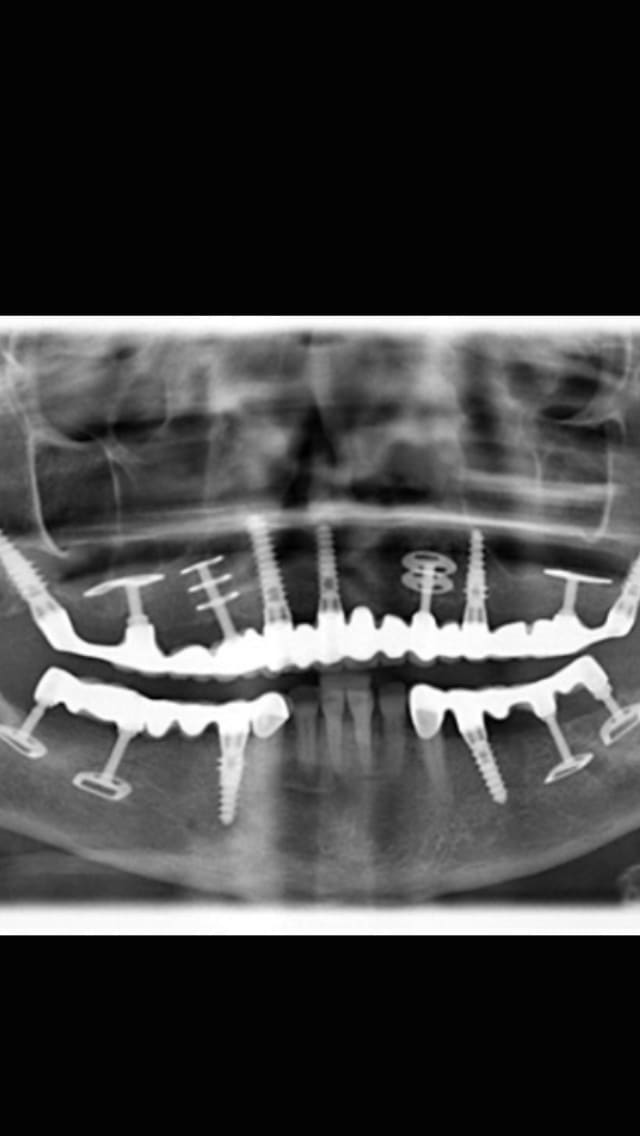

Fallait avoir un certain niveau pour placer ce genre d'implants et avoir peur de rien

Img 1223 cteepu - Eugenol

faut s'appeler scortecci ou shoffler ))))

je susi emeerveillé par ce qu'ils sont arrivés a faire sans l'aide des scan etc